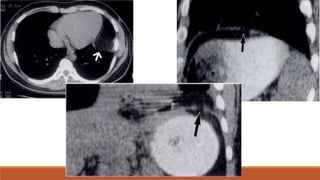

Axial CT scan shows mild irregularity of the

anterior aspect of T12 Sagittal reconstructed

image demonstrates an acute anterior wedge

fracture of T12.

Axial CT scan shows multiple fragments of

the fractured T5 vertebral body. The spinal

canal is narrowed at this level. Sagittal

reconstructed image clearly demonstrates

the loss of vertebral body height and bone

fragments posteriorly displaced into the

spinal canal. The posterior elements are also

fractured.